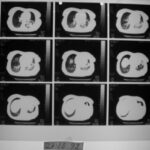

2003: 61 yaşındaki erkek hasta prostat adenokarsinomu ve yaygın kemik metastazı tanısı aldı.

Tuşe rektalde prostat büyümüş ve sertti.

Ağrıları kayboldu, metastaz bulgularında belirgin düzelme görüldü.

Yapılan sintigrafi patolojik bulgu göstermedi.

2005 Ocak: Sintigrafi tamamen normal